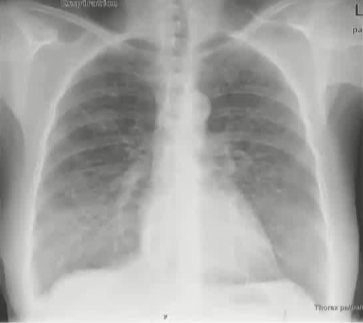

栓塞材料的可及性(例如病灶栓塞材料的可到达性)accessability (e.g. reachability of the nidus) 栓塞的预期深度intended deepness of embolization 如果需要让栓塞填满最后1mm 预期效果(例如:门静脉栓塞的炎症)intended effect (e.g. inflammation in PVE) 凝血状态(达到止血效果所需的时间)coagulation state (duration until hemostasis) 并发症(过敏、心律不齐、肺动脉高压、肝纤维化等)comorbidities (allergies, arrythmia, pulmonary hypertension, lung fibrosis etc.) 处于危险中的结构(包括下游部分-downstream和反流部分) structures at risk (downstream & backwash) 靶病变定位(浅层与深层) target lesion localization (superficial vs. deep) 不会选择一些会引起炎症的东西,因为那会病人来说真的很痛苦浅层病变 栓塞所需的速度(例如:危及生命的出血情况)required speed of embolization (e.g. life threatening hemorraghe) 院外专业人员(DSA技术人员和介入放射科医生)local expertise (technicians & IR's) 可用性与定价 availabilty & pricing Patient assessment for the choice of the ideal liquid emboli 影像学 62岁 男性

腹腔侧支循环

腹水 水肿 jaundice 男性乳腺发育症 多血管蜘蛛状结构(提示存在食管静脉曲张) 肝掌 (palmar erythema) 指表皮或真皮层受刺激后毛细血管扩张引发的局部皮肤发红现象 和患者说话